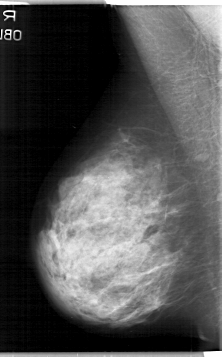

D_4114_1.RIGHT_MLO

RIGHT_CC LINES 5311 PIXELS_PER_LINE 3316 BITS_PER_PIXEL 12 RESOLUTION 43.5 NON_OVERLAY

RIGHT_MLO LINES 5341 PIXELS_PER_LINE 3316 BITS_PER_PIXEL 12 RESOLUTION 43.5 NON_OVERLAY